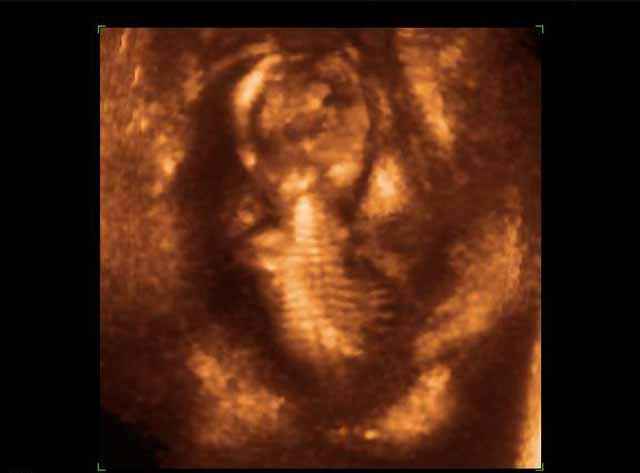

- 3D Photos échographie du squelette du fœtus

3D Photos échographie du squelette du fœtus | Dr N Layyous